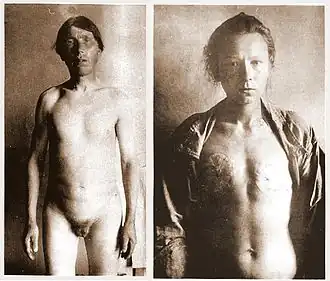

There were two kinds of castration: the "lesser seal" and the "greater seal". For men, the "lesser seal" meant the removal of the testicles only, while the "greater seal" involved either removal of the penis or emasculation (removal of both penis and testicles). Men who underwent the "greater seal" used a cow-horn when urinating. The castrations and emasculations were originally performed with a red-hot iron, called the 'fiery baptism'. However, the skoptsy later transitioned to using knives or razors, with the iron serving only to stop the bloodflow. They also twisted the scrotum, destroying the seminal vesicles and stopping the flow of semen.

In women, the Skoptsy removed the nipples or the whole breasts. Occasionally, they simply scarred the breasts. They also often removed the labia minora and clitoris. They did not use anesthetics.[3]